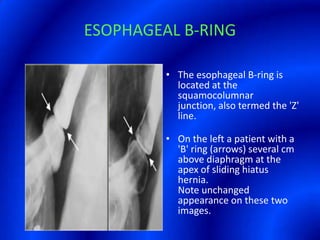

This document provides information about a barium swallow procedure. It begins with an introduction and overview of the embryology and anatomy of the pharynx and esophagus. It then describes the procedure itself, including preparation, technique, views obtained, and indications. Specific conditions that may be examined include pharyngeal and esophageal webs, foreign body impaction, scleroderma, dysphagia, mediastinal masses, and carcinoma. Diagrams are provided to illustrate normal anatomy and various pathological findings.